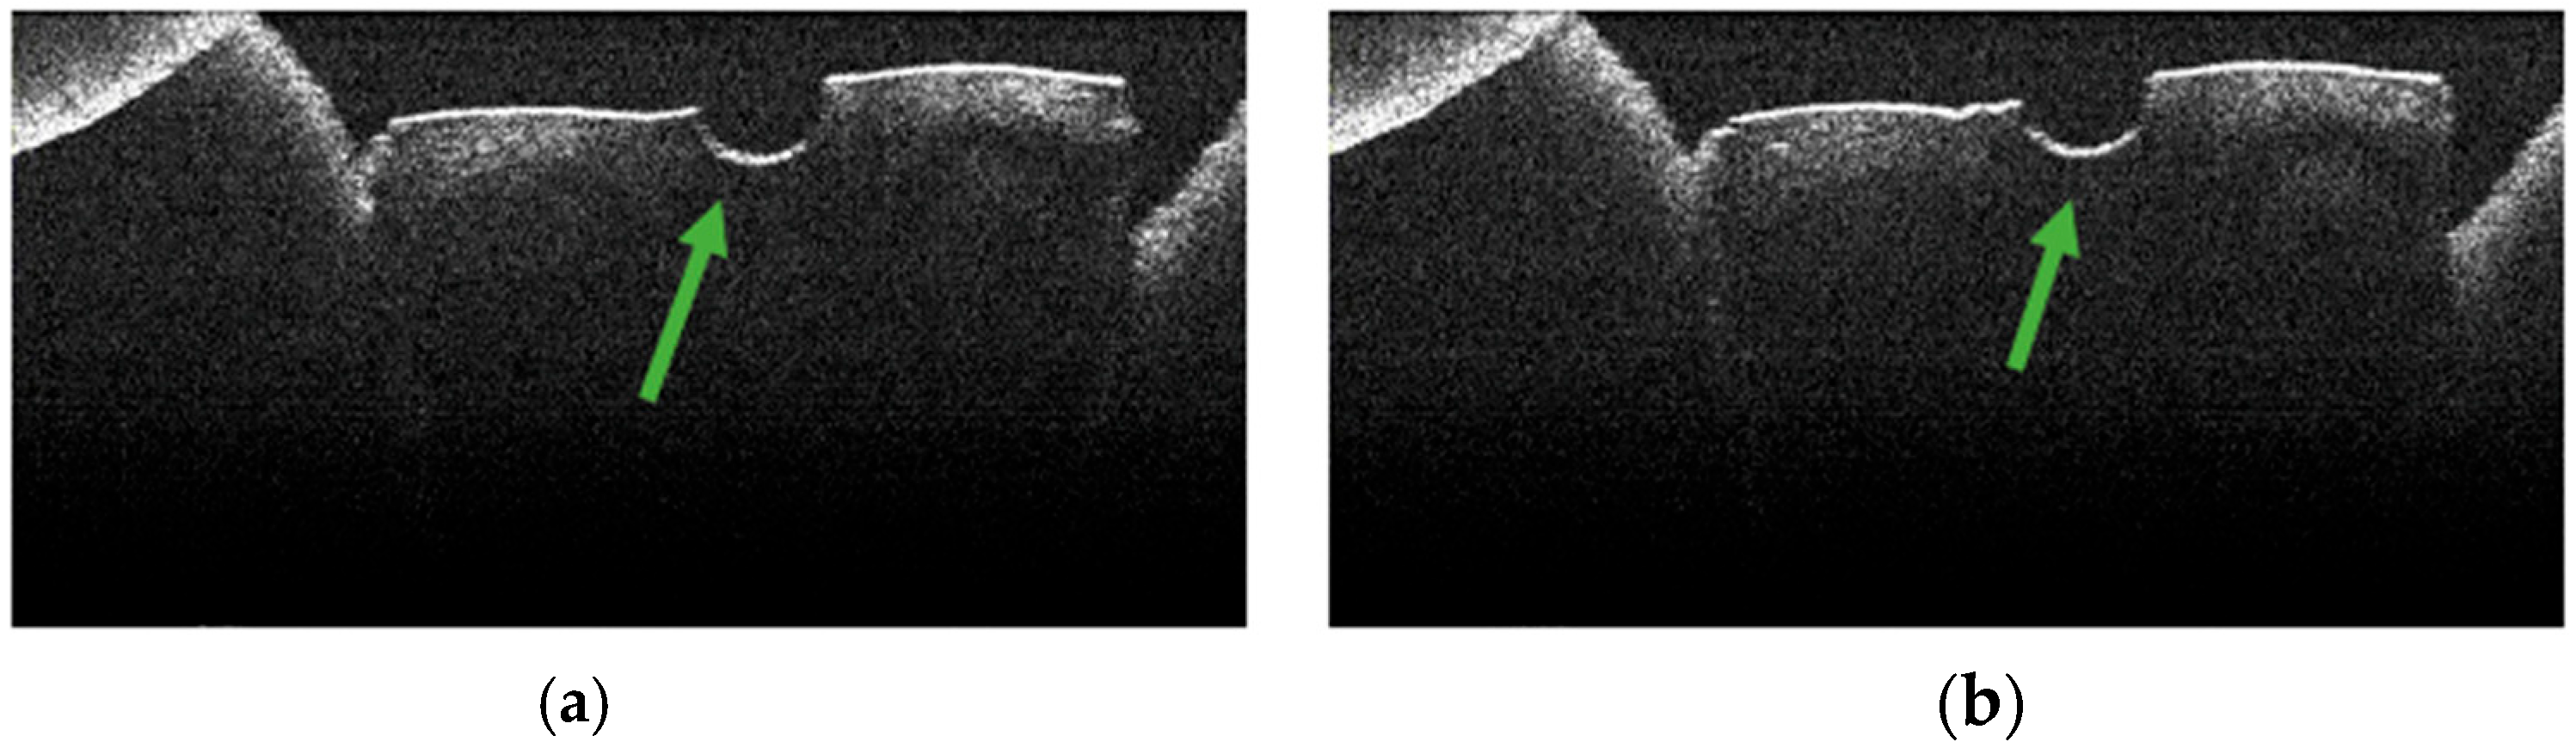

3.4. OCT Examination of Specimens from Group A

3.2. Defining OCT Signatures: Alterations vs. Artefacts